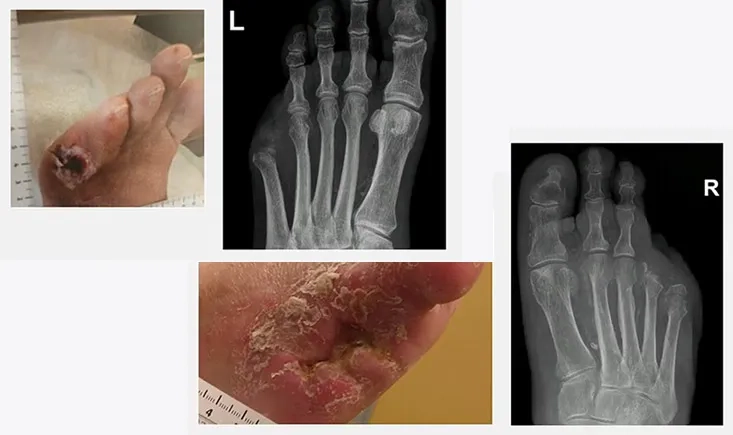

This PVI 2025 symposium explores the role of intravascular lithotripsy (IVL) in below-the-knee (BTK) disease, focusing on heavily calcified lesions. The session reviews how IVL enables low-pressure angioplasty while improving vessel compliance and safety. Through a real-life case, the session discusses when IVL is most useful in BTK/BTA interventions, particularly when scaffolding options are limited. The E8 catheter is highlighted for its improved trackability and ability to treat longer, complex lesions.